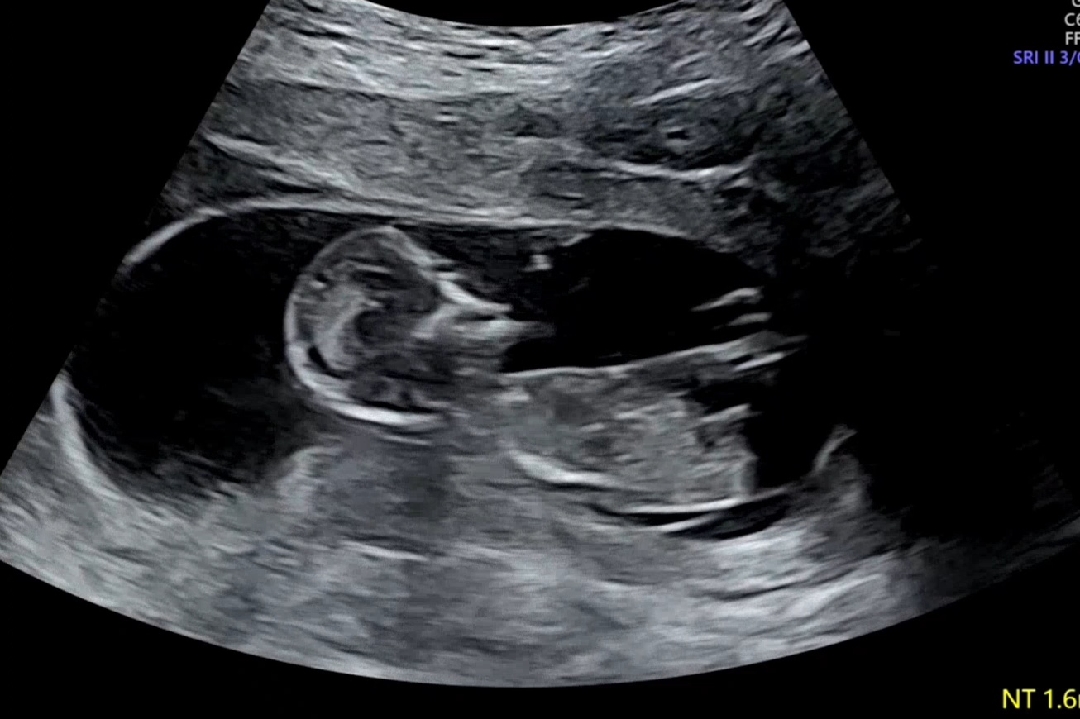

12주6일 각도법 봐주세요!🙏🏻

돌출부가 잘 안보여요ㅠㅠ